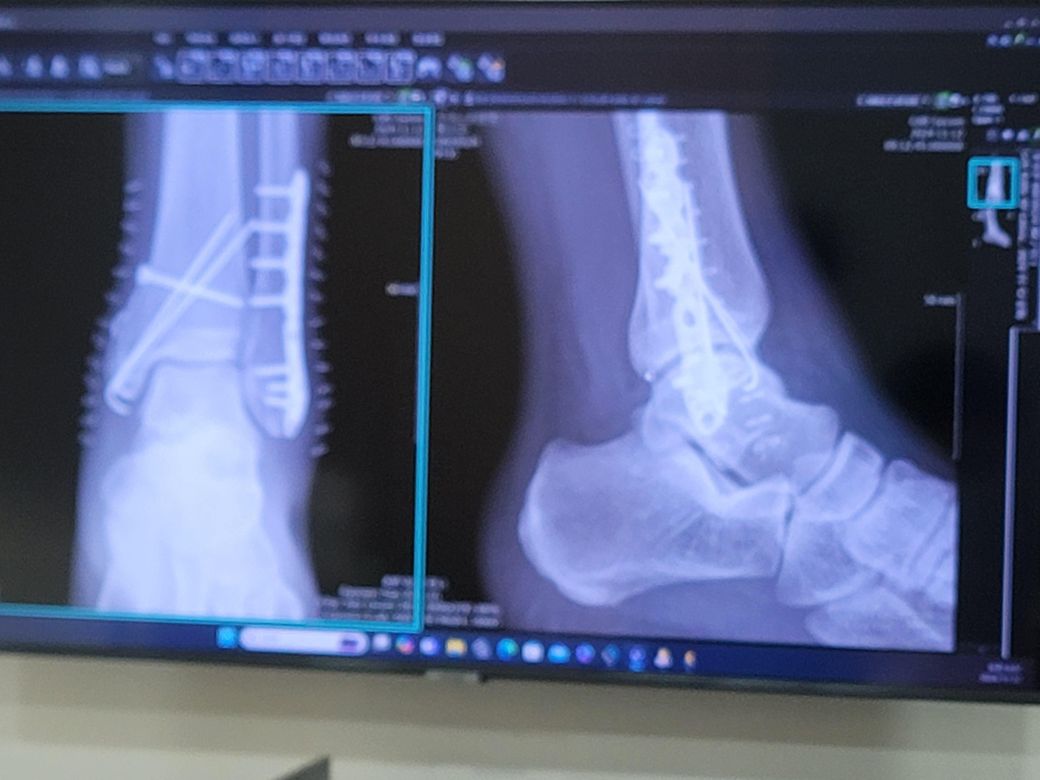

복사뼈 양쪽 골절시 나사가 뼈을 뚫고 나오는게 맞나요?

왼쪽발 복사뼈 양쪽이 부러져 수술을 했는데 바깥쪽에는 철판을 고정해서 나사을 박고 안쪽에는 나사을 박아서 철사줄로 땡겨서 나사을 대각선으로 2개을 박아서 고정했는데 나사길이가 뼈두께을 뚫고 나왔는데 바깥쪽은 붓는게 별로 없는데 안쪽은 걸으면 붓고 자고 일어나서 아침에는 빠지고 하는데 나사가 뼈을 뚫고나와서 걸을때 나사끝이 뼈사이 조직을 찔러서 그런건가요?

• 1번 째 사진

나사 길이가 뼈 두께를 뚫고 나왔다는 점과 관련해, 나사가 뼈를 넘어서 나왔다면 조직 자극이나 통증을 유발할 수 있으며 일반적으로, 나사가 너무 깊게 박혀서 뼈를 지나쳐 나왔을 때는 주변 조직, 특히 근육이나 인대, 혈관, 신경 등을 자극할 수 있습니다.

나사 끝이 뼈를 뚫고 나온 상태에서 조직을 찔러서 통증이나 부종이 발생할 수 있습니다. 특히 발을 움직일때 나사 끝이 주변 조직을 자극하면서 붓기나 불편함을 초래할 수도 있고 나사 끝이 조직을 자극하면서 염증이 발생하면서 부종이나 통증이 발생하기도 합니다.